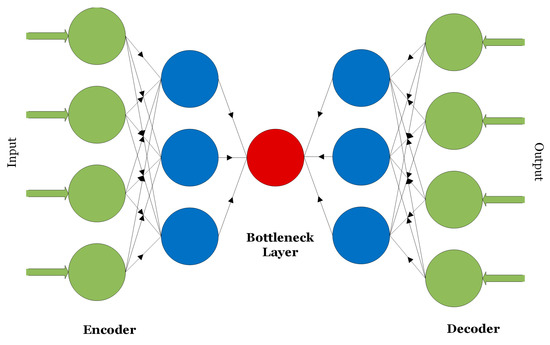

Autoencoders are unsupervised learning techniques consisting of a pair of encoder and decoder units as shown in Figure 4 [14]. Generally, autoencoders are used to compress or transform high-dimensional data into low-dimensional signatures.

Figure 4.

The encoder–decoder structure of an autoencoder.

Inputs to autoencoders can be one-dimensional data that is partially corrupted with noise as in de-noising autoencoders or multi-dimensional data as in convolutional autoencoders.